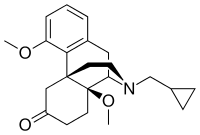

Functional selectivity

A new strategy of drug development takes receptor signal transduction into consideration. This strategy strives to increase the activation of desirable signalling pathways while reducing the impact on undesirable pathways. This differential strategy has been given several names, including functional selectivity and biased agonism. The first opioid that was intentionally designed as a biased agonist and placed into clinical evaluation is the drug oliceridine. It displays analgesic activity and reduced adverse effects.[162]